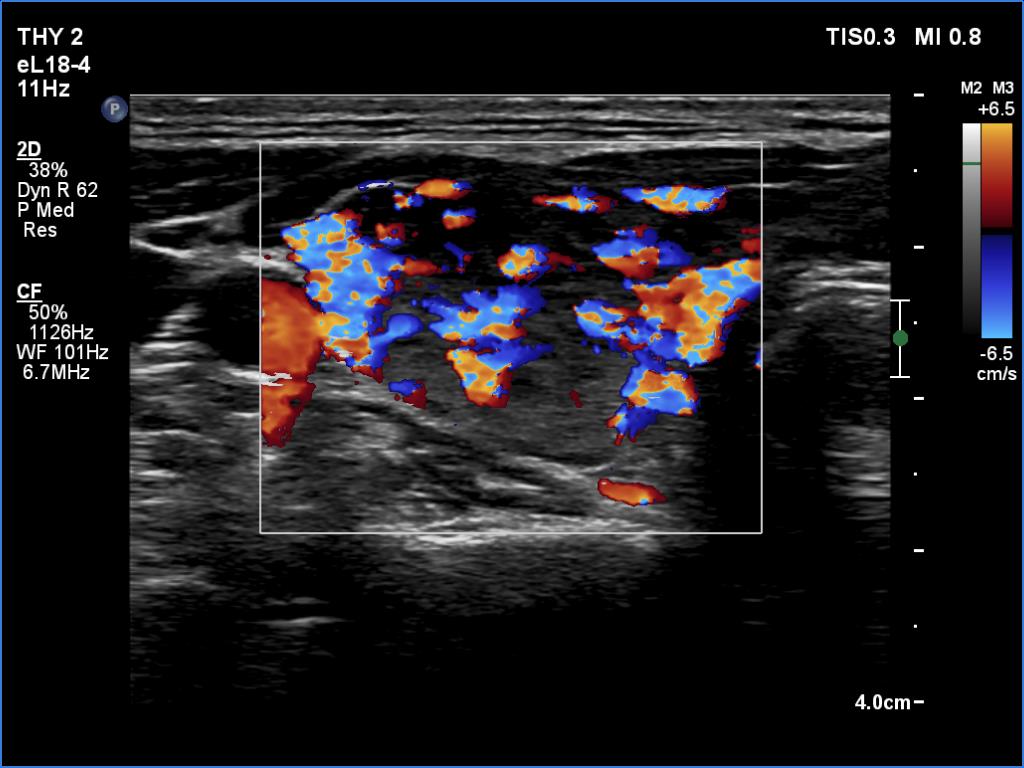

Right lobe, transverse scan

Right lobe, color Doppler mode